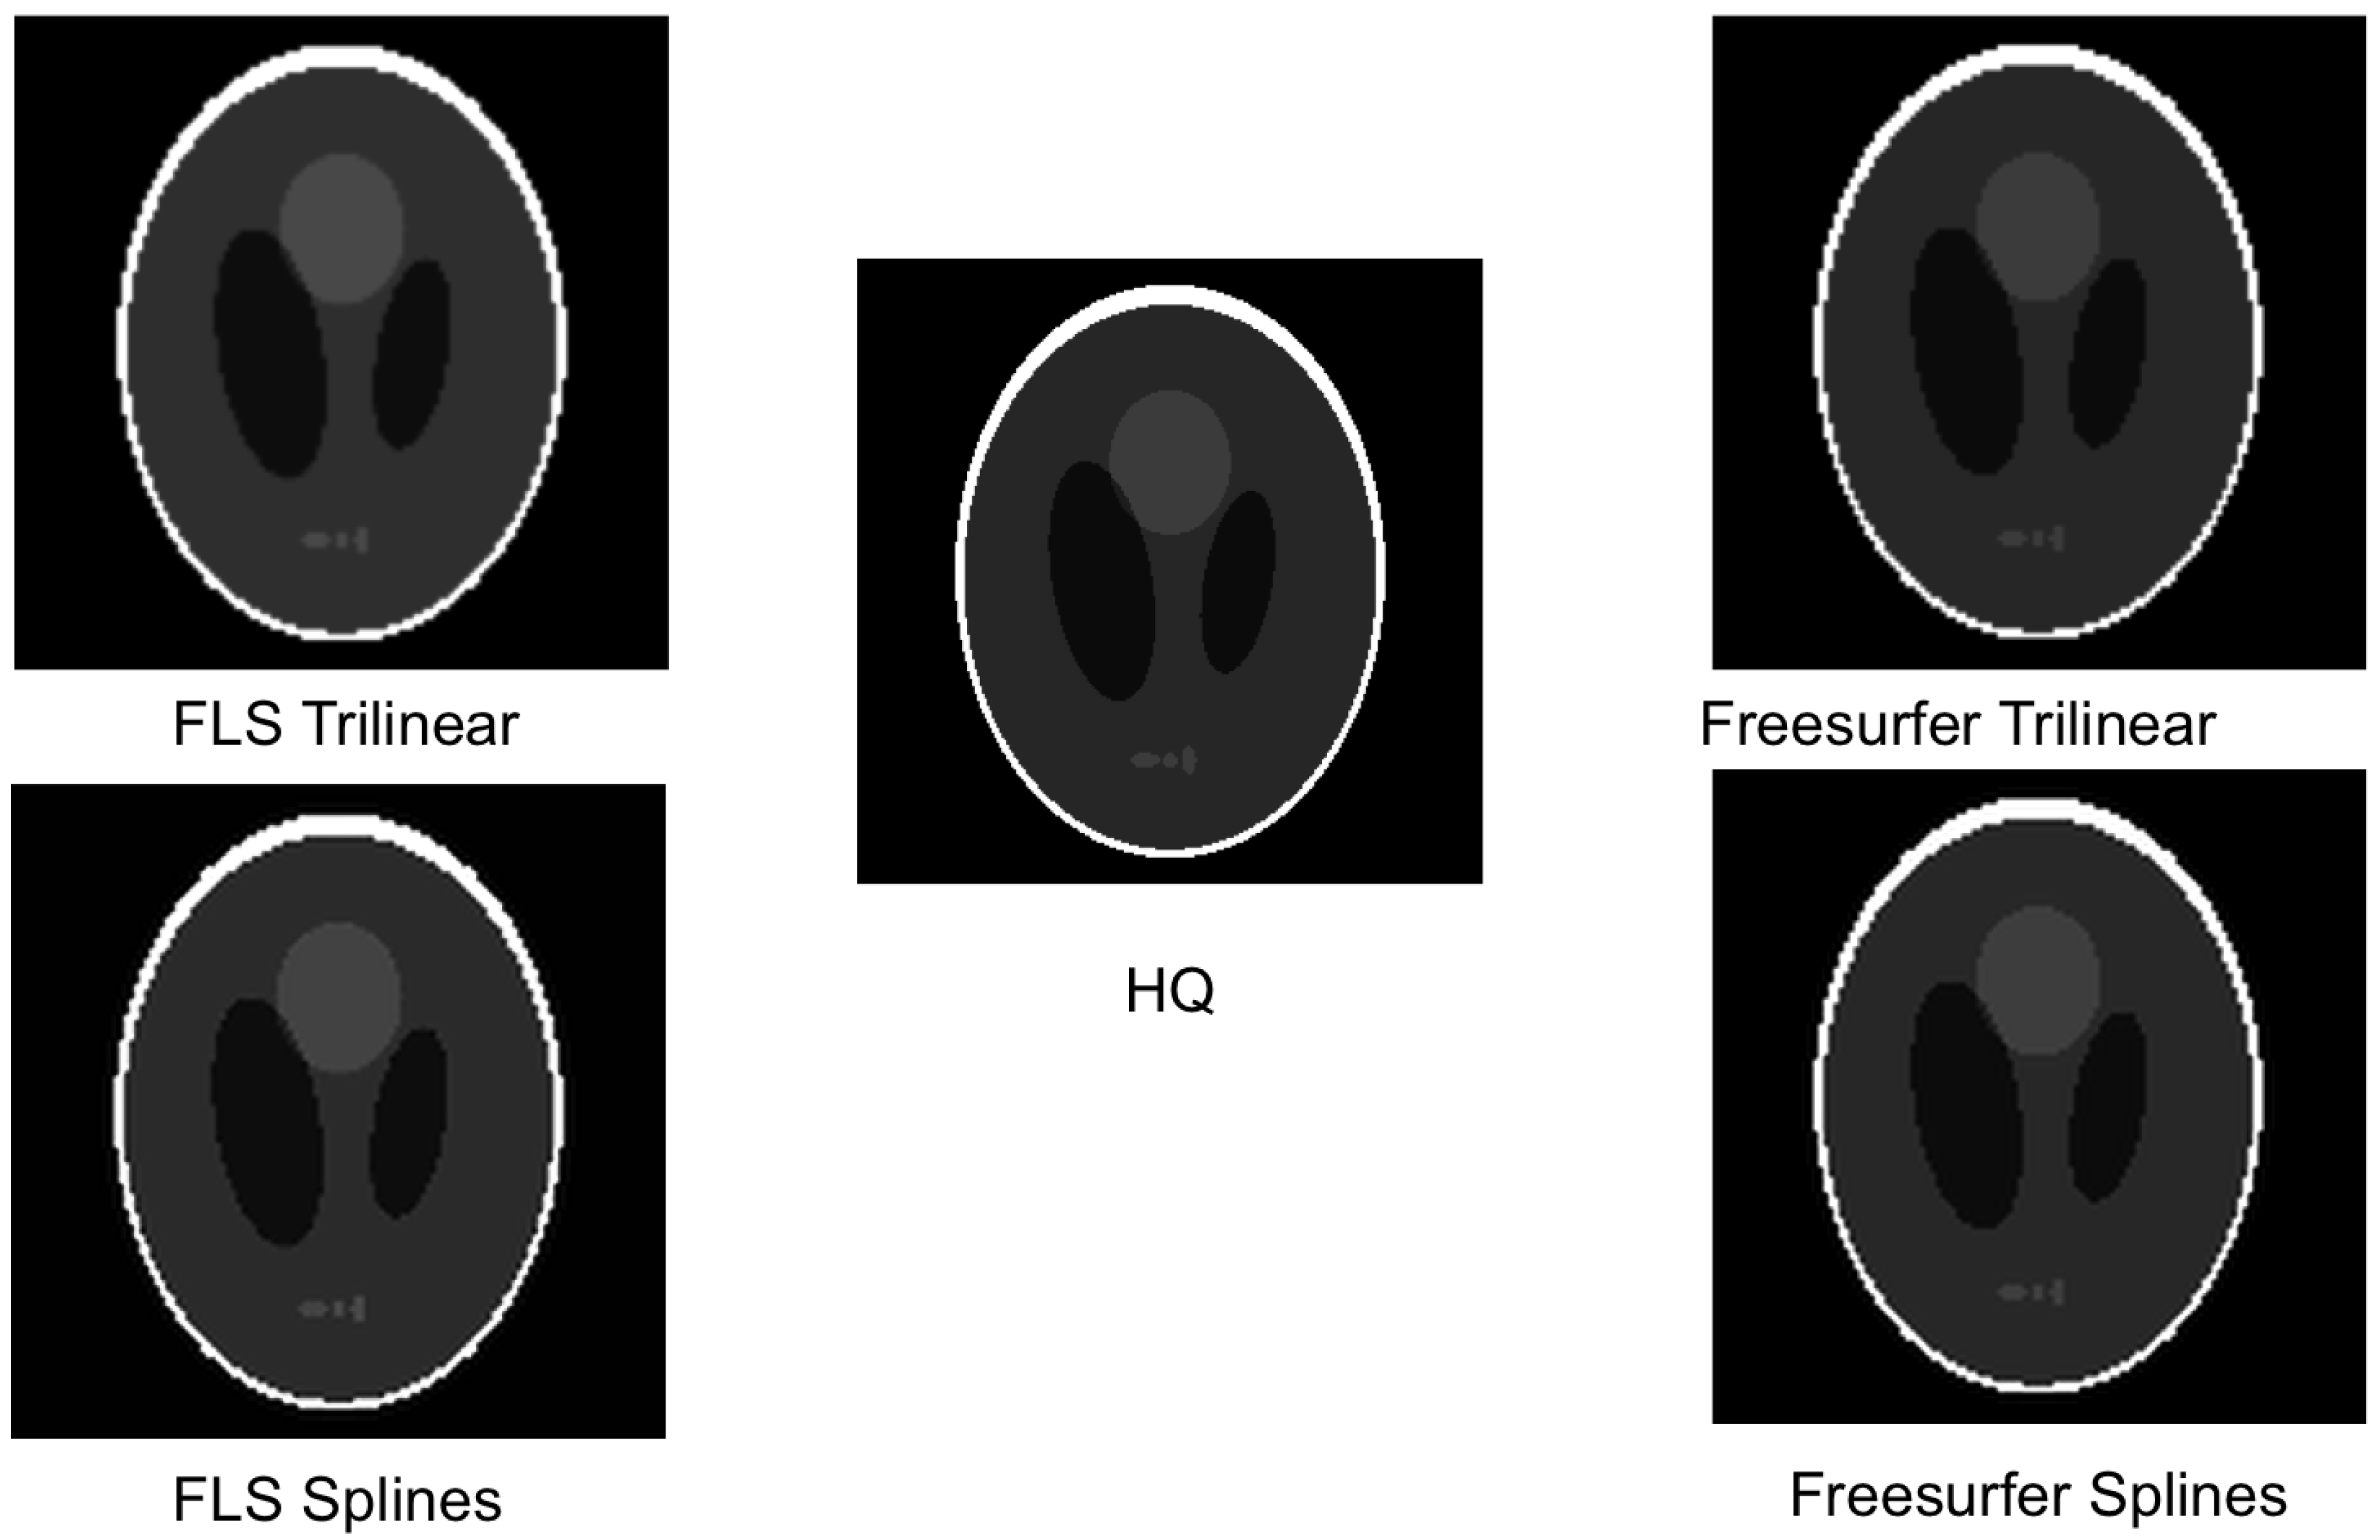

- The 3D Shepp–Logan (SL) phantom [26], a picewise-constant function made by the weighted sum of characteristic functions over different ellipsoids. The SL images were created in python with tomopy and nibabel [27] and saved in nifti format. The Segmention was made with a python script by grouping the voxels of the same intensity values. Size: ;

- antsApplyTransforms from Advanced Normalization Tools (ANTs) [31,32] v2.2.0, with interpolation options:

- Linear, Gaussian, LanczosWindowedSinc and Splines for oversampling functional image;

- Trilinear and Splines for oversampling;

- Trilinear and Splines for oversampling.